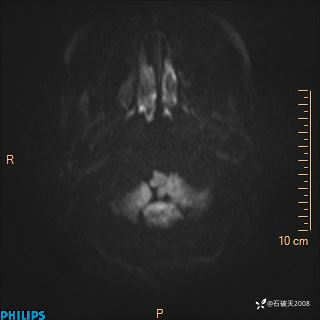

DWI

ADC